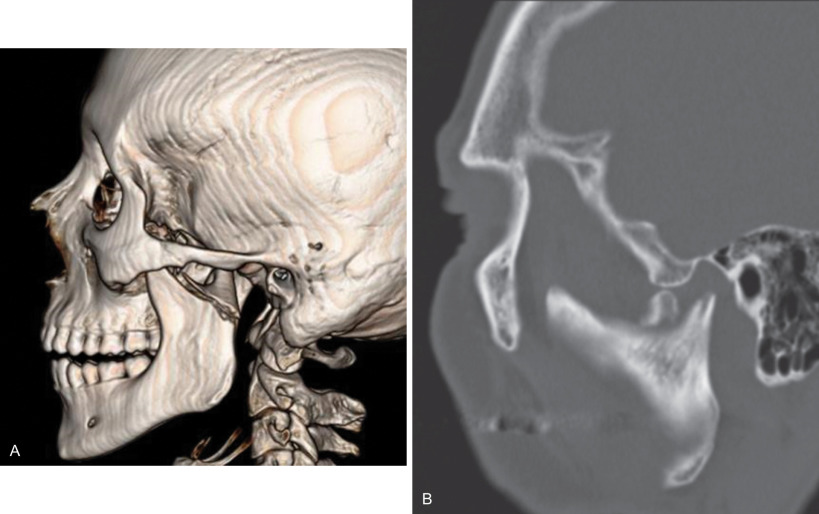

Diacapitular (fractures). This is another European term that is used when the fracture line starts at the articular surface, goes through the head of the condyle and may extend outside the capsule. So it extends from within the capsule to outside the capsule ( Fig. 1.15.9 ). These types of fractures are also known as intracapsular fractures , especially in North America. However, it has been shown that in a large number of “intracapsular” fractures, the fracture extends inferior to the capsule on the medial aspect. The name “intracapsular ” therefore may be anatomically incorrect in such cases.

CT of a diacapitular fracture. Note that the fracture line begins on the articular surface, goes through the head of the condyle and may extend outside the joint capsule on the medial side.